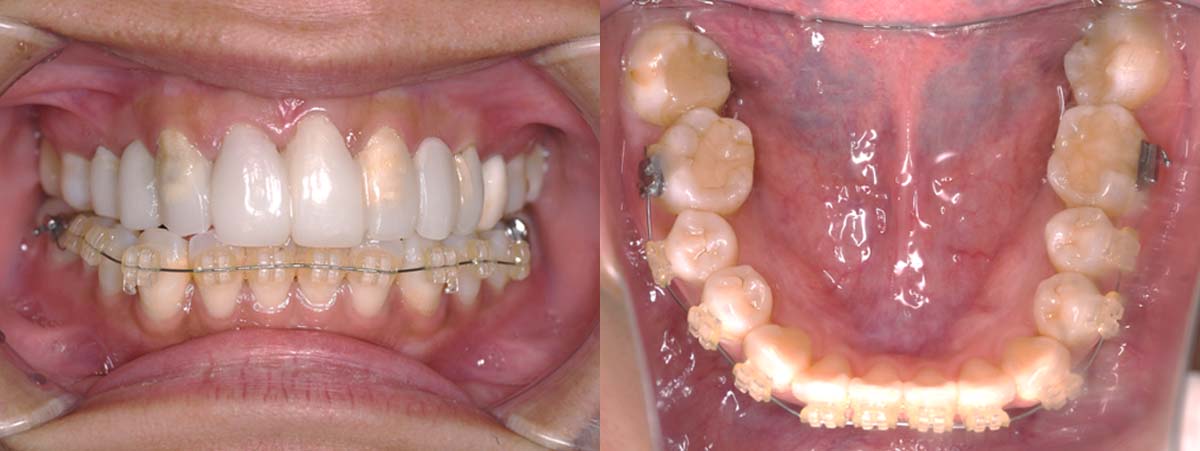

| 治療内容 | ①スプリントを装着 ②副子を装着 ③2024年4月 口腔内反映開始 ④副子を入れた状態の所まで咬合を挙上 (バイトアップ) ⑤2024年5月 上顎前歯部8本へ仮歯(TEK) を装着 |

2024年 10月 下顎MTM開始

2024年 10月10日